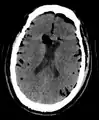

| Pneumocephalus and comminuted fracture of the frontal sinus |

CT scans of patients with a tension pneumocephalus typically show air that compresses the frontal lobes of the brain, which results in a tented appearance of the brain in the skull known as the Mount Fuji sign.[1][2][3] The name is derived from the resemblance of the brain to Mount Fuji in Japan, a volcano known for its symmetrical cone. In typical cases, there is a symmetrical depression near the midline (such as the crater of a volcano), due to intact bridging veins.[3] Its occurrence seems to be limited to tension pneumocephalus (not occurring in pneumocephalus without tension).[4] The sign was first described by a team of Japanese neurosurgeons.[5]